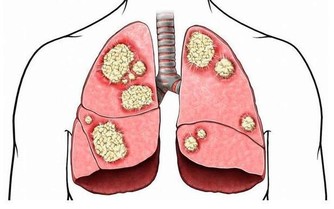

這個病名很專業,可能很多非血液科的醫生都沒聽到過。說直白點,就是患者的造血幹細胞惡性克隆,導致無效造血。白血病,我們通常稱之為血癌,骨髓增生異常綜合征其實也是一種血液腫瘤。這種病預後很差,有30%左右的患者會發展為白血病。

研究認為,苯是染髮劑中最基本的化學物質,對造血系統具有強烈毒性。染髮劑使用一個階段后,苯會沿頭髮浸入頭皮毛細血管,破壞造血系統,引起頭暈、乏力、皮下、內臟和腦出血,更加嚴重的是誘發癌症。近年來,醫學界常使用「染髮白血病」這個名詞,表明了染髮與白血病的關係。